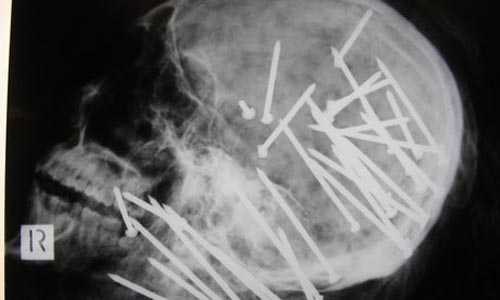

![]() |

| Đinh găm chi chít trong đầu người từ một cây súng bắn đinh |